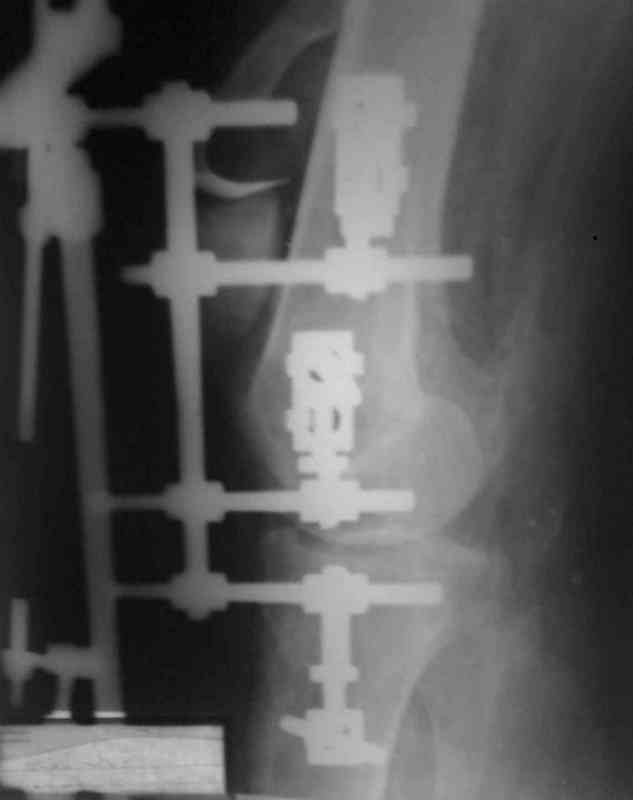

Bolnoi 27 let, DTP, Motorcycle trauma, postupil v kreane tiajelom

sostoianii, osnovnia trauma- otkrity totalny vyvih levogo kolennogo

sustava s povrezhdeniem malogo bertsovogo nerva, trakcionnot povrezdenie

podkolennoi arterii bez narushenia tselostnost' sosuda, pomosh' okazana

v nujnum obeme, kakoe ze mnenie uvazaemih kolleg naschet dalneshego

vedenia bolnogo?